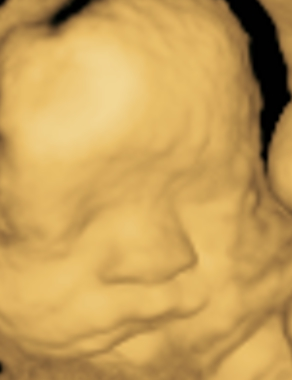

Contamos con gran variedad de estudios como abdomen, pélvico, tiroides, obstétrico 3D y 4D, protocolos maternofetales, estructural, entre otros.

MATERNO FETAL

PERFIL BIOFÍSICO FETAL